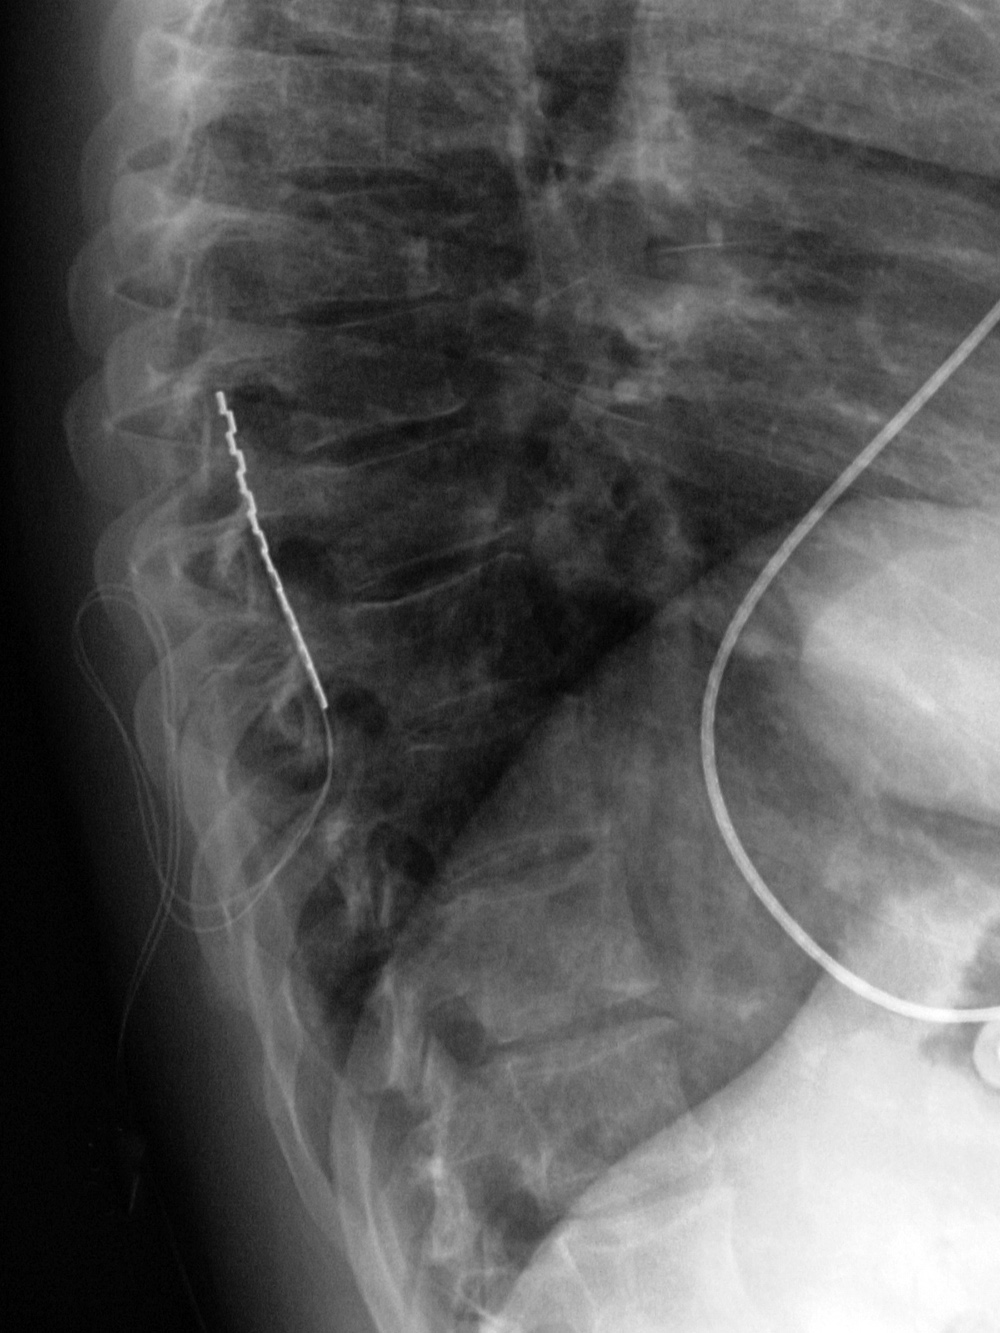

| Vertebroplasty at L1 and L3 (AP view) |

Vertebroplasty at L1 and L3 (lateral view) |

Vertebroplasty is designed to provide pain relief from benign osteoporotic compression fractures or less common, destructive vertebral lesions (Cotten, 1998; Hulme, 2006; Petscavage-Thomas, 2014; McConnell, 2014). Methyl methacrylate is injected directly into a vertebral body to strengthen the bone structure of the vertebra and immobilize fractures, which provides immediate pain relief. If the patients are properly selected and the procedure goes well, vertebroplasty is a dramatic technique. Patients who are bedridden or wheelchair bound have such relief from the chronic

pain of vertebral collapse that they frequently ask to walk out of the hospital. Vertebroplasty is a

serious procedure, and patients must be carefully selected. Because the methyl methacrylate is

mixed with barium sulfate, it is visible on radiographs and on cross-sectional images (figure: vertebroplasty).